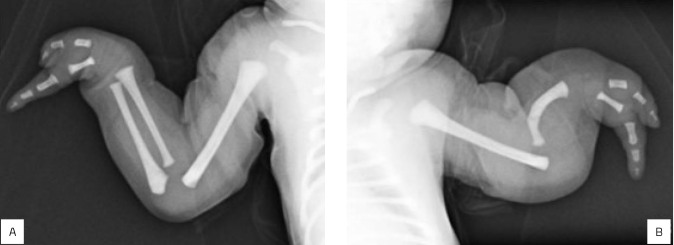

Bilateral ulnar longitudinal deficiency with oligodactyly in newborn.

Case description: A full-term male newborn, born following an uncomplicated gestation with no abnormalities detected on prenatal ultrasounds, presented upper limb malformations described as shortening of the left forearm and absence of three digits bilaterally upon neonatal physical examination. Diagnostic investigations including X-rays, abdominal ultrasound, head ultrasound, echocardiogram, and karyotype analysis were conducted, facilitating detailed identification of the malformations and exclusion of other anomalies, thereby suggesting the diagnosis of congenital longitudinal deficiency of the ulna. Discharge planning encompassed supportive care and rehabilitation as per the patient's needs.

Comments: Ulnar longitudinal deficiency is a rare congenital upper limb malformation, whose estimated incidence is 1:100,000 newborns. It is believed to be related to the Sonic Hedgehog gene, and the upper limb anomalies vary according to the ulnar involvement. The early diagnosis is not routine, being more common at the first physical examination with the aid of imaging tests.